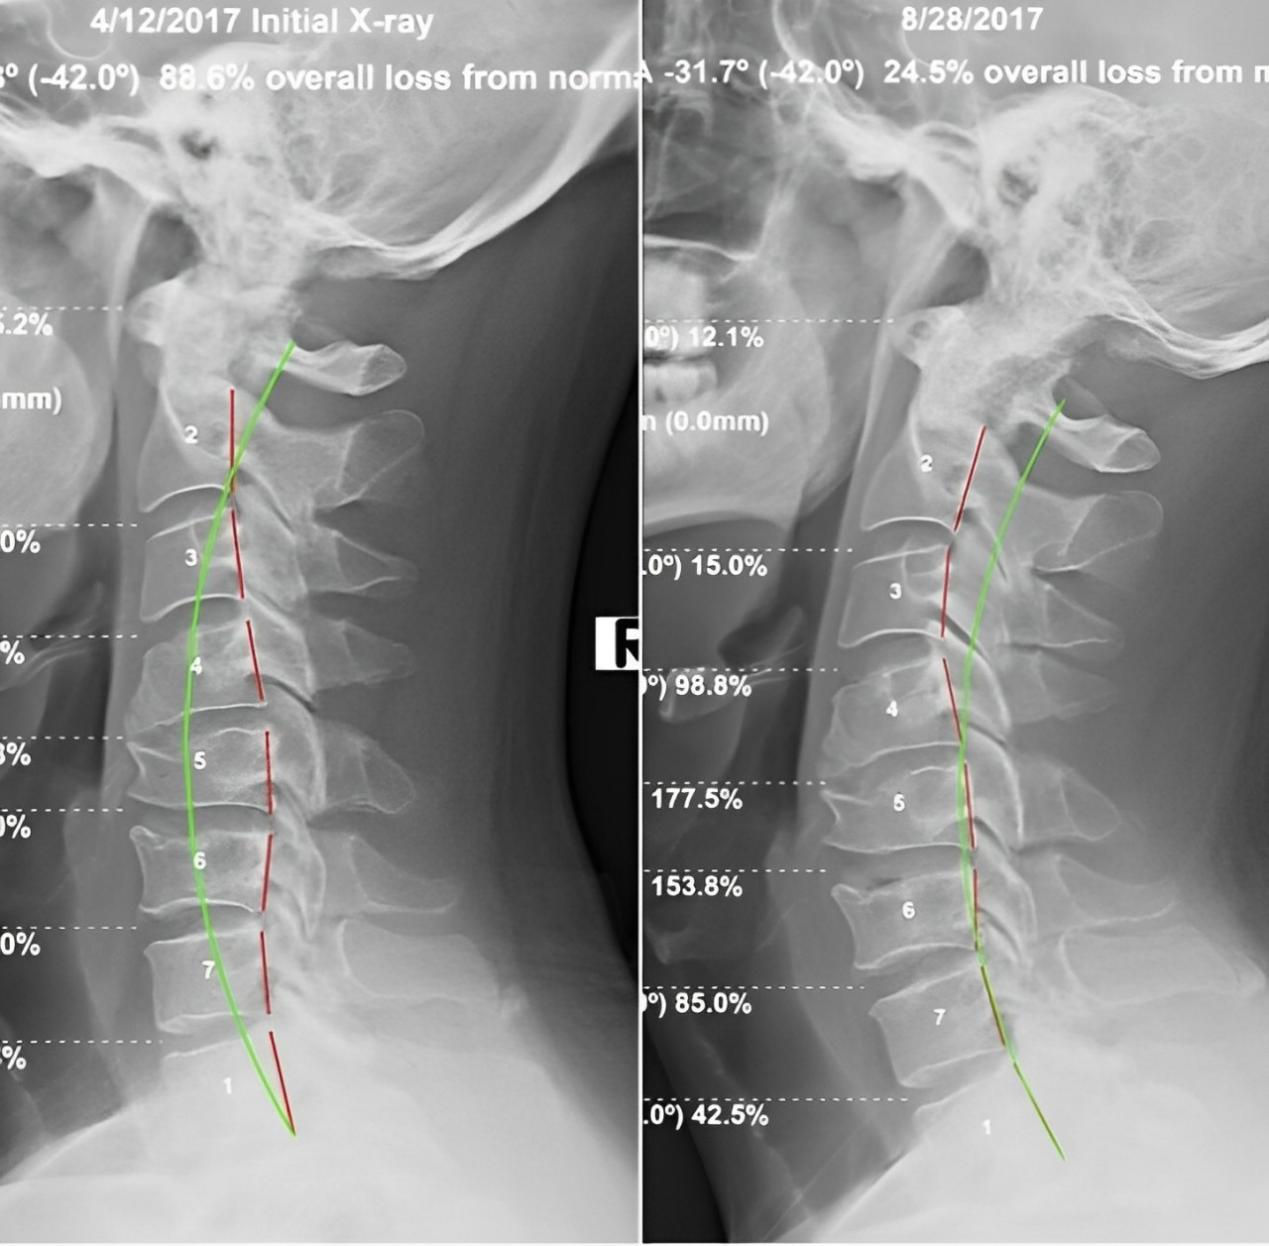

四、 恢復脊椎自然曲度

脊椎整復床的獨特設計能夠幫助恢復脊椎的自然曲度,改善脊椎側(cè)彎和不良姿勢,讓您重獲健康體態(tài)。

五、矯正完和矯正后的對比案例: